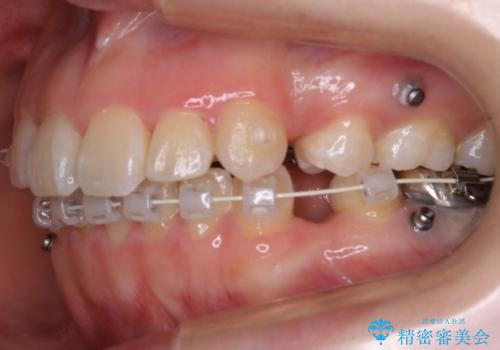

ハーフリンガル装置

ワイヤー矯正の中でも、上顎を裏側・下顎を表側に装置をつけて動かす方法をハーフリンガルといいます。

ハーフリンガルを選択すると、ワイヤー矯正の利点である抜歯ケースへの対応が可能な点と、表側の装置の欠点である装置が目立つという点をカバーして矯正治療を進めることができます。

表側の装置と違い、使えるワイヤーの種類に制限があり平均治療期間が長くなりやすい点、装置の作製自体の金額が掛かることから費用面で表側装置よりも高額になるという点はマイナスポイントであるといえますが、しっかりと口元を下げたり、噛み合わせの構築を行うことは遜色なく行えるため人気のある装置となっております。

また、裏側に装置が付くことによって喋り辛さを感じる方もいらっしゃいます。